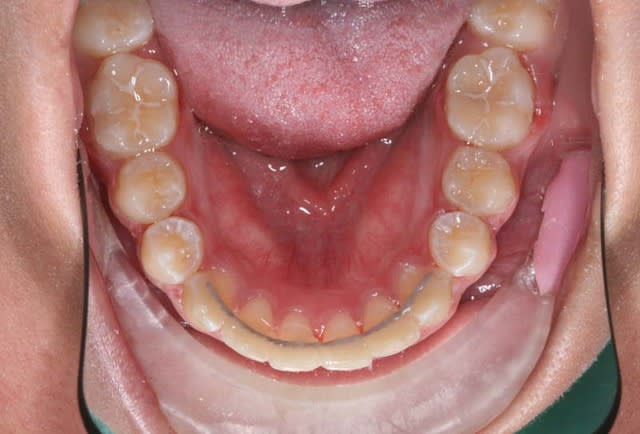

2°) phase

Friction faible avec ressorts de Root

6 lddvd2 - Eugenol

3°) phase

contention

@+ Bjc